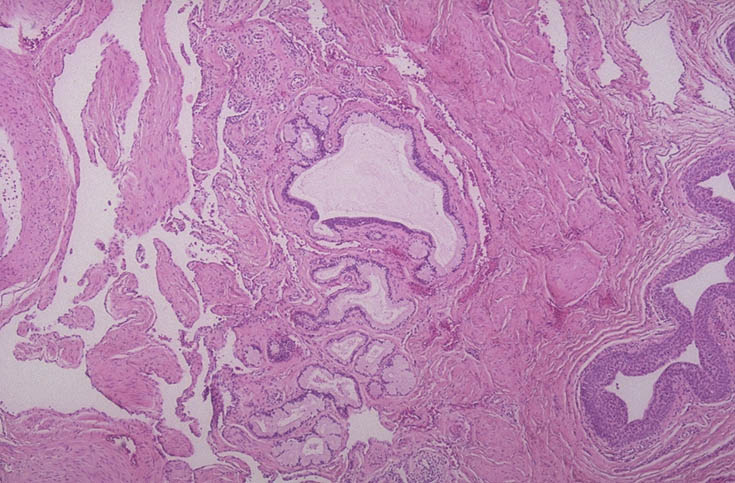

| The bulbourethral (Cowper's) gland is a paired structure about 0.5 cm in size located on either side of the urethra in the urogenital diaphragm below the prostate in males, consisting of small mucinous glands surrounded by bulbocavernosus muscle and draining via a duct lined by cuboidal to transitional epithelium into the urethra. These glands supply mucinous secretions. A higher power view is seen below. |